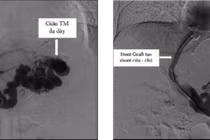

Chỉ trong chưa đầy 24 giờ, bệnh nhân đã phải truyền gần 2,5–3 lít chế phẩm máu. Sau khi huyết áp tạm ổn định, nội soi tiêu hóa khẩn cấp ghi nhận giãn tĩnh mạch thực quản độ III đã vỡ — biến chứng đặc biệt nguy hiểm thường gặp ở bệnh nhân xơ gan do tăng áp lực tĩnh mạch cửa.

Ê-kíp của Trung tâm nội soi và thăm dò chức năng của Bệnh viện đã tiến hành thắt nhiều vòng cao su để cầm máu, tuy nhiên tình trạng chảy máu vẫn có nguy cơ tái phát do rối loạn đông máu nặng trên nền suy gan mạn tính.